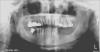

Здраствуйте ! Склоняюсь к тому, чтобы поставить бугельный протез с телескопическими коронками. Что посоветуете в моей ситуации ? И прокомментируйте пожайлуста ; какие зубы мне стоит удалить и что делать с мостом.  Он меня вполне устраивает. Подвижность зубов II степени. Импланты не по карману.

post-34740-0-49033400-1374073496_thumb.jpg